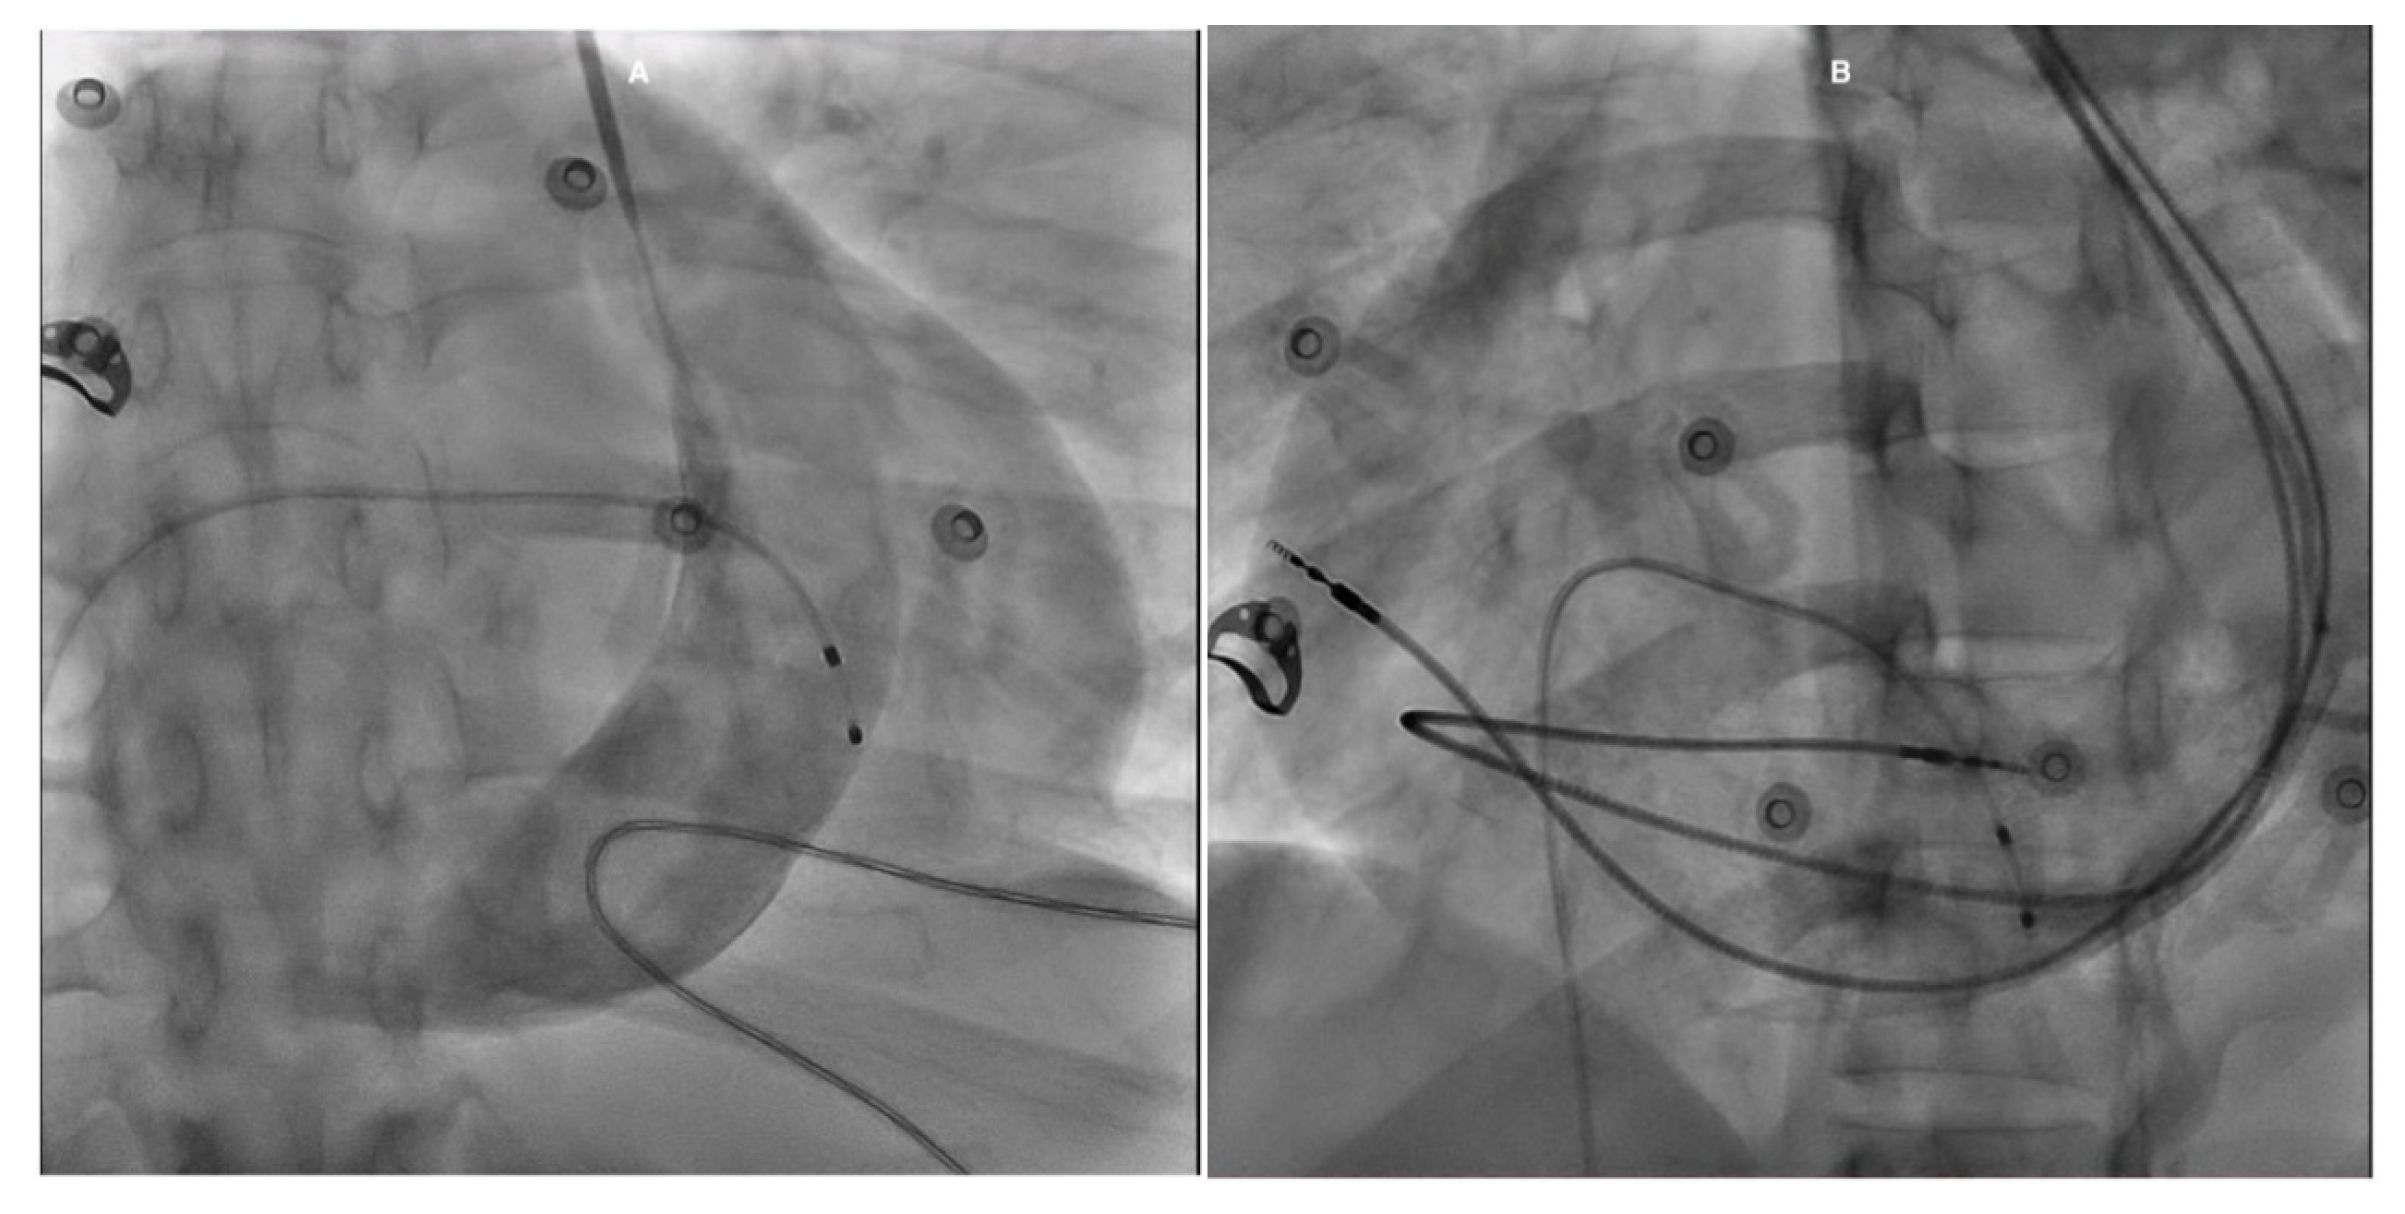

The patient was admitted to the intensive care unit for CHB and stabilized with a temporary pacemaker (PM). An ECG after temporary PM insertion showed ventricular pacing spikes (Fig. 2). Given the need for continuous stimulation and a mildly reduced LVEF, the patient was subsequently referred for cardiac resynchronization therapy with a pacemaker (CRT-P). In the catheterization laboratory, a left pectoral incision was made; however, the guide wire followed the trajectory of a PLSVC. Contrast injection to assess possible LV lead placement revealed only a single, very small branch of the CS, which was considered insufficient for lead insertion. As a result, the management plan was revised, and CRT-P was deemed unfeasible. Instead, a dual-chamber PM was implanted (Fig. 3).

Figure 3: Fluoroscopy images in the RAO view with contrast show a large CS associated with a PLSVC (A). In the LAO view, the RA lead is positioned in the lateral wall, while the RV lead follows a large curvature due to its course through the RA before turning into the RV (B). RAO: Right anterior oblique; CS: Coronary sinus; PLSVC: Persistent left superior vena cava; LAO: Left anterior oblique; RA: Right atrium; RV: Right ventricle.